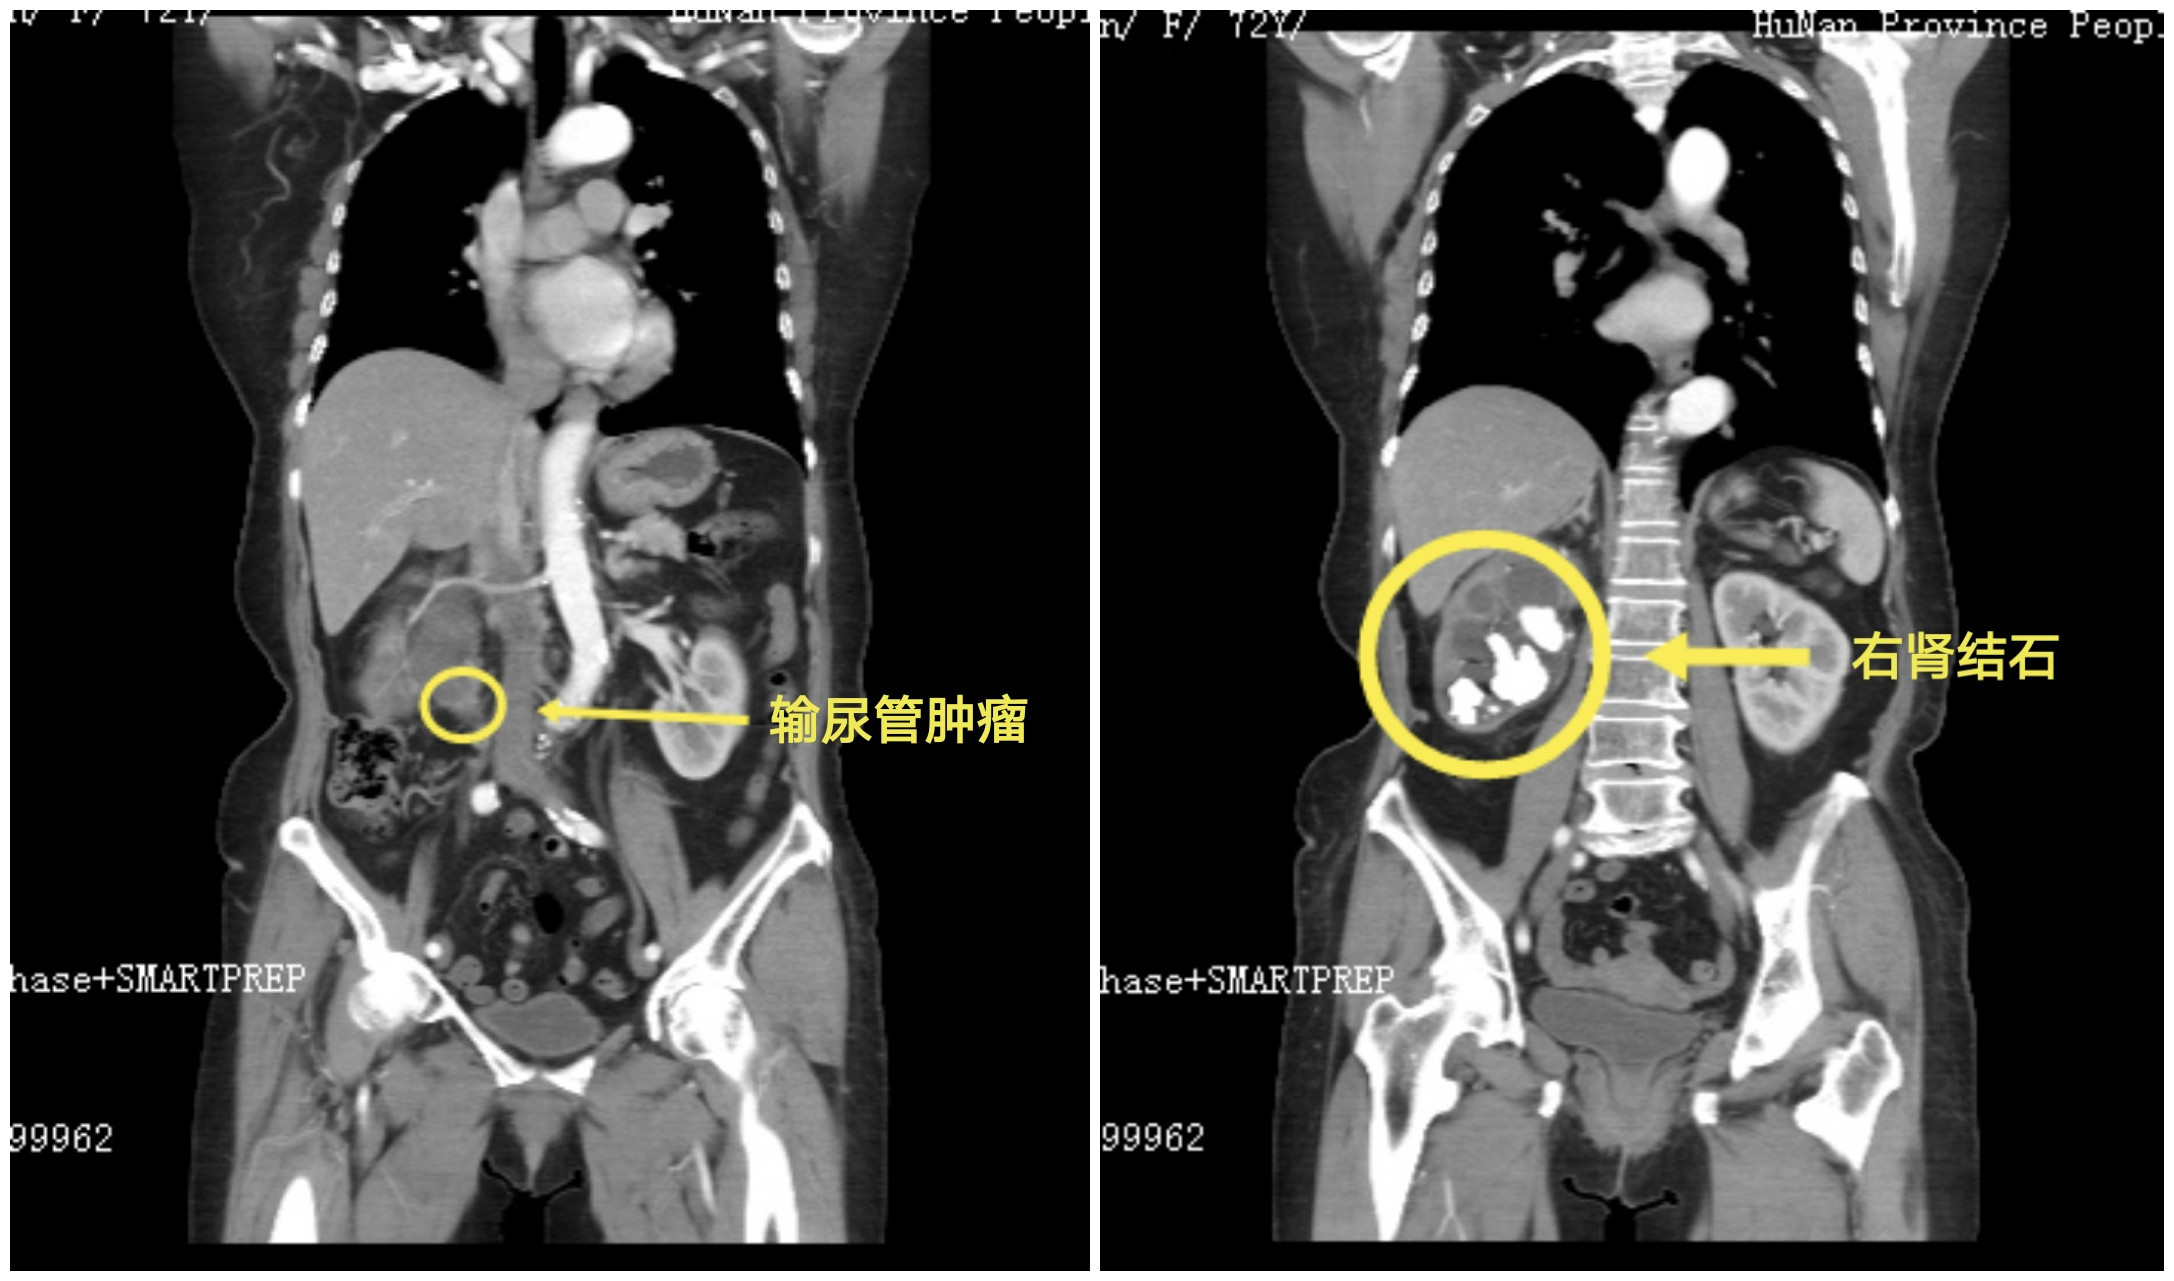

左奶奶早在40多年前就检查出右肾结石,但因无明显症状,几十年来没有定期复查更未进行任何治疗,直到1个月前感觉右侧腰胀、下腹疼痛,伴有血尿的情况,在家人劝说下才到医院看病。经检查发现,左奶奶不仅有右肾结石伴积水和感染,在肾盂输尿管交界处还发现了异常的软组织影,考虑输尿管癌。无论是输尿管癌,还是右肾结石,都需要尽快手术治疗,否则将严重威胁老人的生命健康。

考虑左奶奶年龄大,同时伴有冠心病、高血压病等多种基础疾病,杨科主任组织科室进行病例讨论,确定详细的诊疗方案,通过输尿管镜在左奶奶右侧输尿管上段肾盂交界处发现花生大肿瘤。